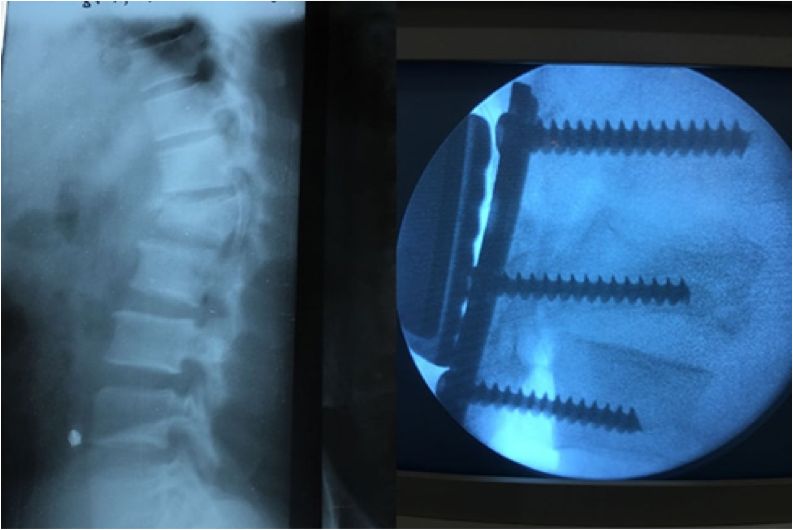

Venimos anunciando nuestra intención de iniciar la cirugía de la columna vertebral en 2018.

La ocasión se presentó con un paciente que tenía una grave fractura vertebral con una parálisis en miembro inferior. El Dr. Areta tuvo el coraje de operarle con los materiales de los que disponemos (actualmente no específicos para la cirugía de raquis) con un fantástico resultado y con una progresiva recuperación de la movilidad y fuerza muscular en su pierna paralizada.

• Hemos realizado la primera cirugía vertebral.